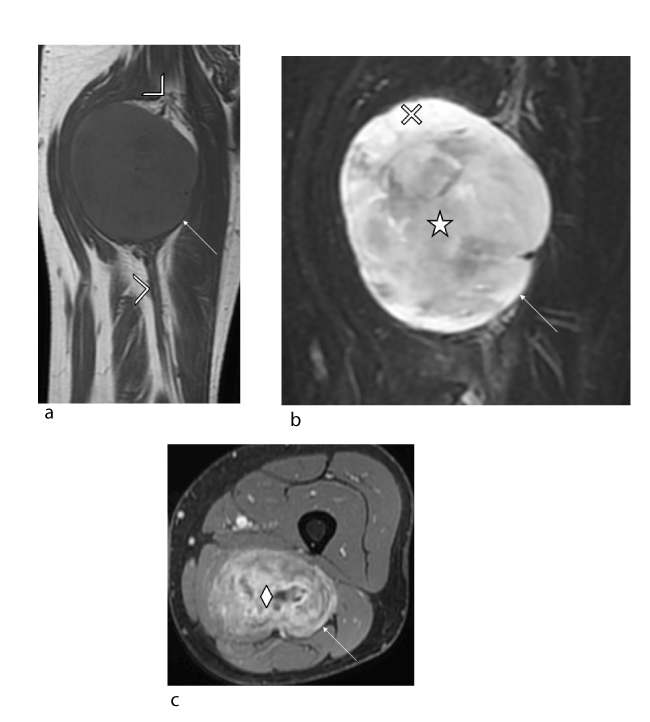

Figure 6. Young female patient (11 years old) with isolated deficit in the territory of the common peroneal nerve: intraneural perineurioma of the left sciatic nerve confirmed histologically. (a, b) Coronal T1 (TR/TE 592/10) and coronal STIR (TR/TE 3445/15) slices showing local, crude hypertrophy of the sciatic nerve with T1 isosignal and STIR hyperintensity (arrow) with no spread to adjacent soft tissues. (c) Axial T1-weighted fat-suppressed post-gadolinium slice showing homogeneous uptake in the tumour (arrow) which is off-centred relative to the sciatic nerve (arrowhead).